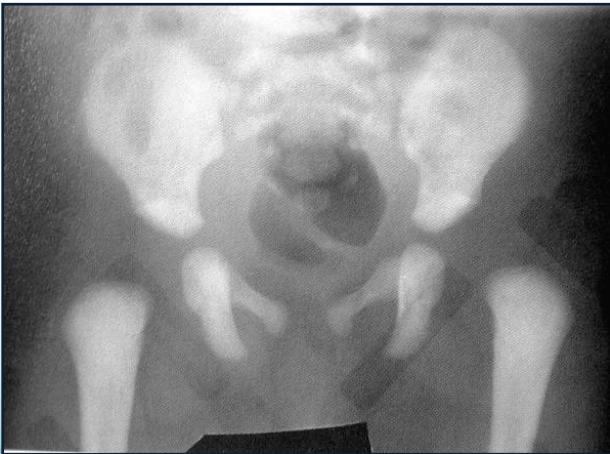

After 6 Months

- Clearly shows dislocation

- Femoral head ossific center size and position assessment

Radiological Assessment Methods

1. Horizontal Line Through Tri-radiate Cartilage

- Normal: Femoral head ossific center below the horizontal line

- Dislocated: Femoral head ossific center above the horizontal line

2. Perpendicular Line from Acetabular Edge

- Normal: Femoral head ossific center medial to perpendicular line

- Dislocated: Femoral head ossific center lateral to perpendicular line

3. Acetabular Index (Acetabular Angle)

- Measurement: Angle from acetabular edge to base at horizontal line

- Normal: ≤ 25°

- Dislocated: > 35°

4. Shenton’s Line

- Important assessment tool for hip joint integrity